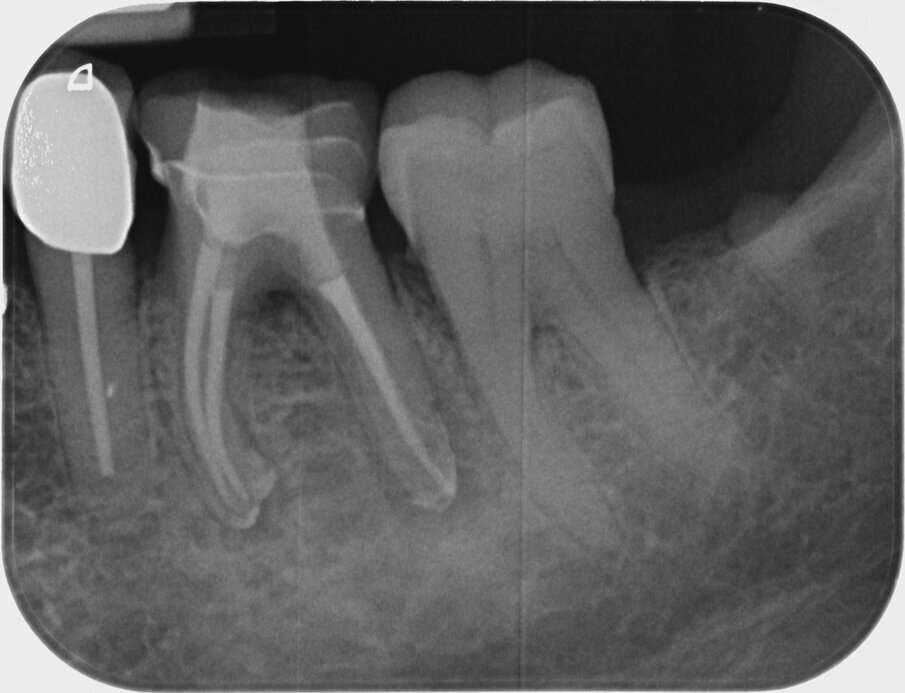

After preparation of the glide path, the following HyFlex EDM sequence was used: first the 20/.05 instrument, then the 25/~ HyFlex EDM OneFile and finally the 40/.04 file in all canals (Figs. 7–10). An acoustic signal from the endodontic motor indicated when rinsing should ideally be performed to remove the abraded debris from the canal. Obturation was performed with a bioceramic sealer (BioRoot RCS, Septodont) using the single-cone technique (Figs. 11–13). The contrast image with the master points and the final radiographic check after obturation demonstrated preservation of the canal anatomy and maintenance of the original path of the canal (Figs. 14–16).

Fig. 15: Radiographic check without cover filling.

Fig. 16: Radiographic check with cover filling.